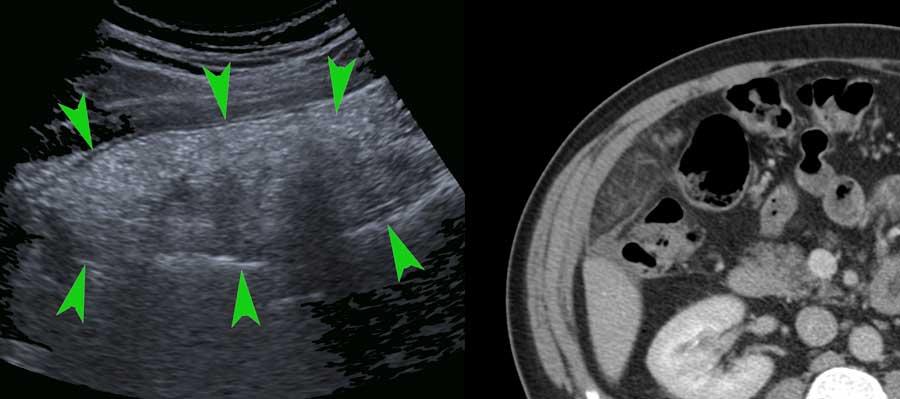

Siêu âm cũng có thể hiển thị mạc nối (đầu mũi tên) trong nhồi máu mạc nối khu trú, trong đó mạc nối bị phù nề do nhồi máu xuất huyết tĩnh mạch.